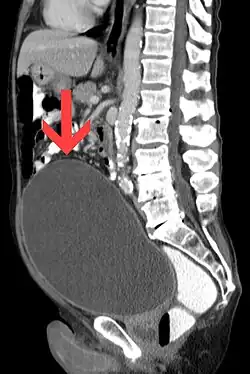

| Urinary retention with greatly enlarged bladder as seen by CT scan. | |

Analysis of urine flow may aid in establishing the type of micturition (urination) abnormality. Common findings, determined by ultrasound of the bladder, include a slow rate of flow, intermittent flow, and a large amount of urine retained in the bladder after urination. A normal test result should be 20–25 ml/s peak flow rate. A post-void residual urine greater than 50 ml is a significant amount of urine and increases the potential for recurring urinary tract infections. In adults older than 60 years, 50-100 ml of residual urine may remain after each voiding because of the decreased contractility of the detrusor muscle.[7] In chronic retention, ultrasound of the bladder may show massive increase in bladder capacity (normal capacity is 400-600 ml).